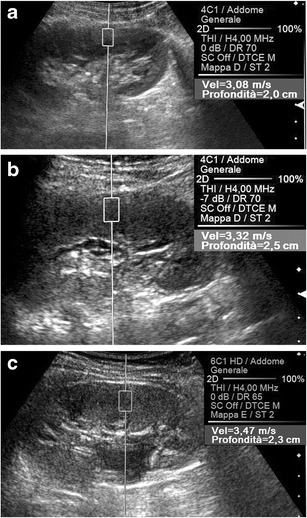

Fig. 12.

ARFI evaluation of kidney. Oblique US scans on the left kidney of three different 12-year-old boys. The cortical SWV value is lower (3.08 vs. 3.47 m/s) in a healthy control (a) than in a boy with chronic kidney disease due to vesicoureteral reflux (c) treated at younger age. Intermediate SWV values (3.32 m/s) are measured in the apparently normal left kidney (b) of a boy with chronic contralateral disease